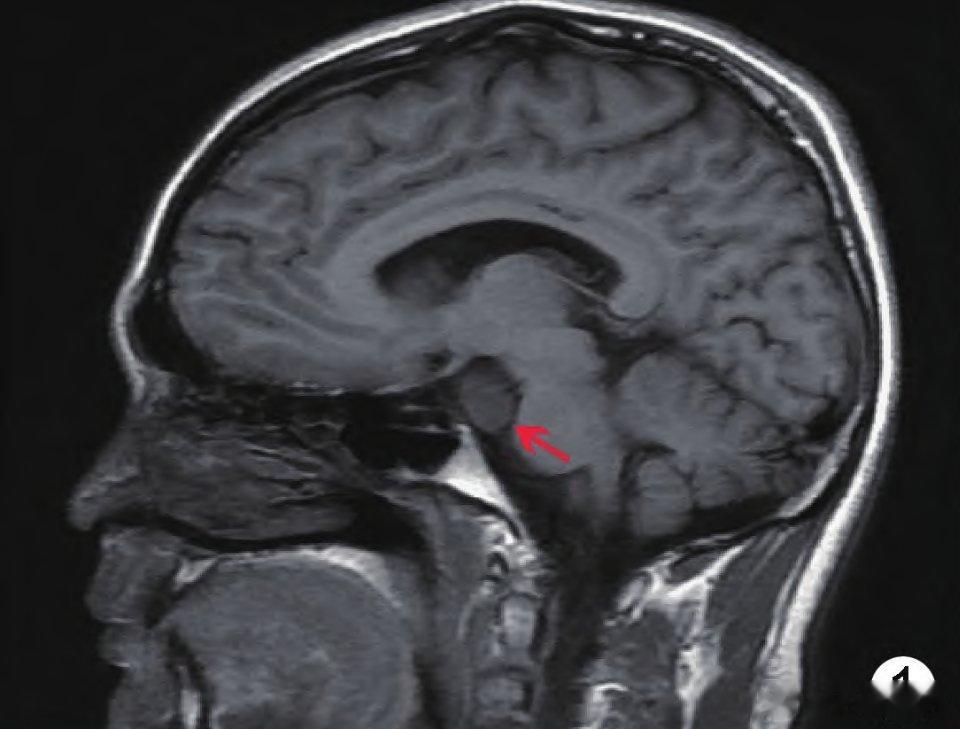

下丘脑错构瘤又称灰结节错构瘤,为临床罕见的颅内先天性畸形,多发于儿童,主要表现为体内雌激素水平过高、第二性征发育早、骨龄增加及伴有无诱因的痴笑发作。

有专家认为下丘脑错构瘤起源于乳头体或灰结节,是正常脑组织形成的异位肿块,组成此种畸形的神经细胞类似于灰结节中的神经组织,并伴有正常胶质细胞。下丘脑错构瘤并非真正的肿瘤,没有生长性,但是能够严重影响儿童正常的身体发育。